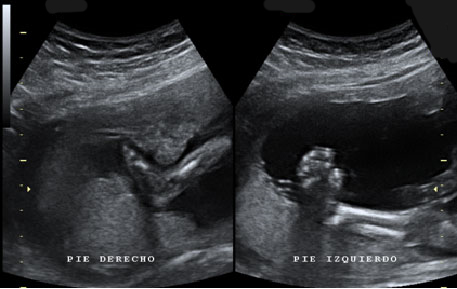

Ecografía Embarazo 2D y 3D Semana 20 - MALFORMACIONES FETALES